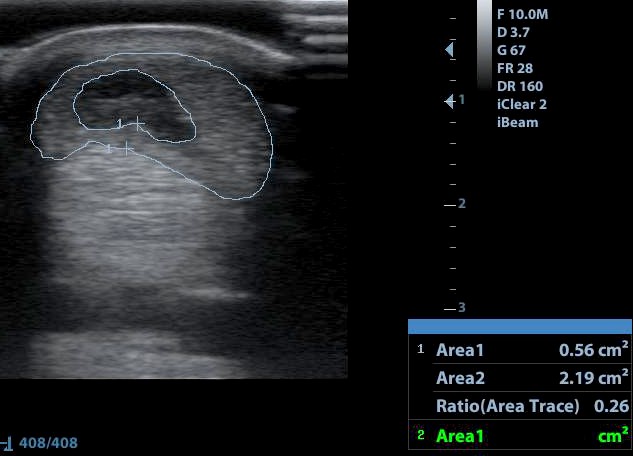

A bal oldalon az ín ép része, a jobb oldalon a sérült fele.

Egy kifejezetten nagy defekt az ín közepében.

A defektet bejelölve lemértük, hogy hány százalékát teszi ki a teljes keresztmetszetnek - jelen esetben 26%-os sérülés.